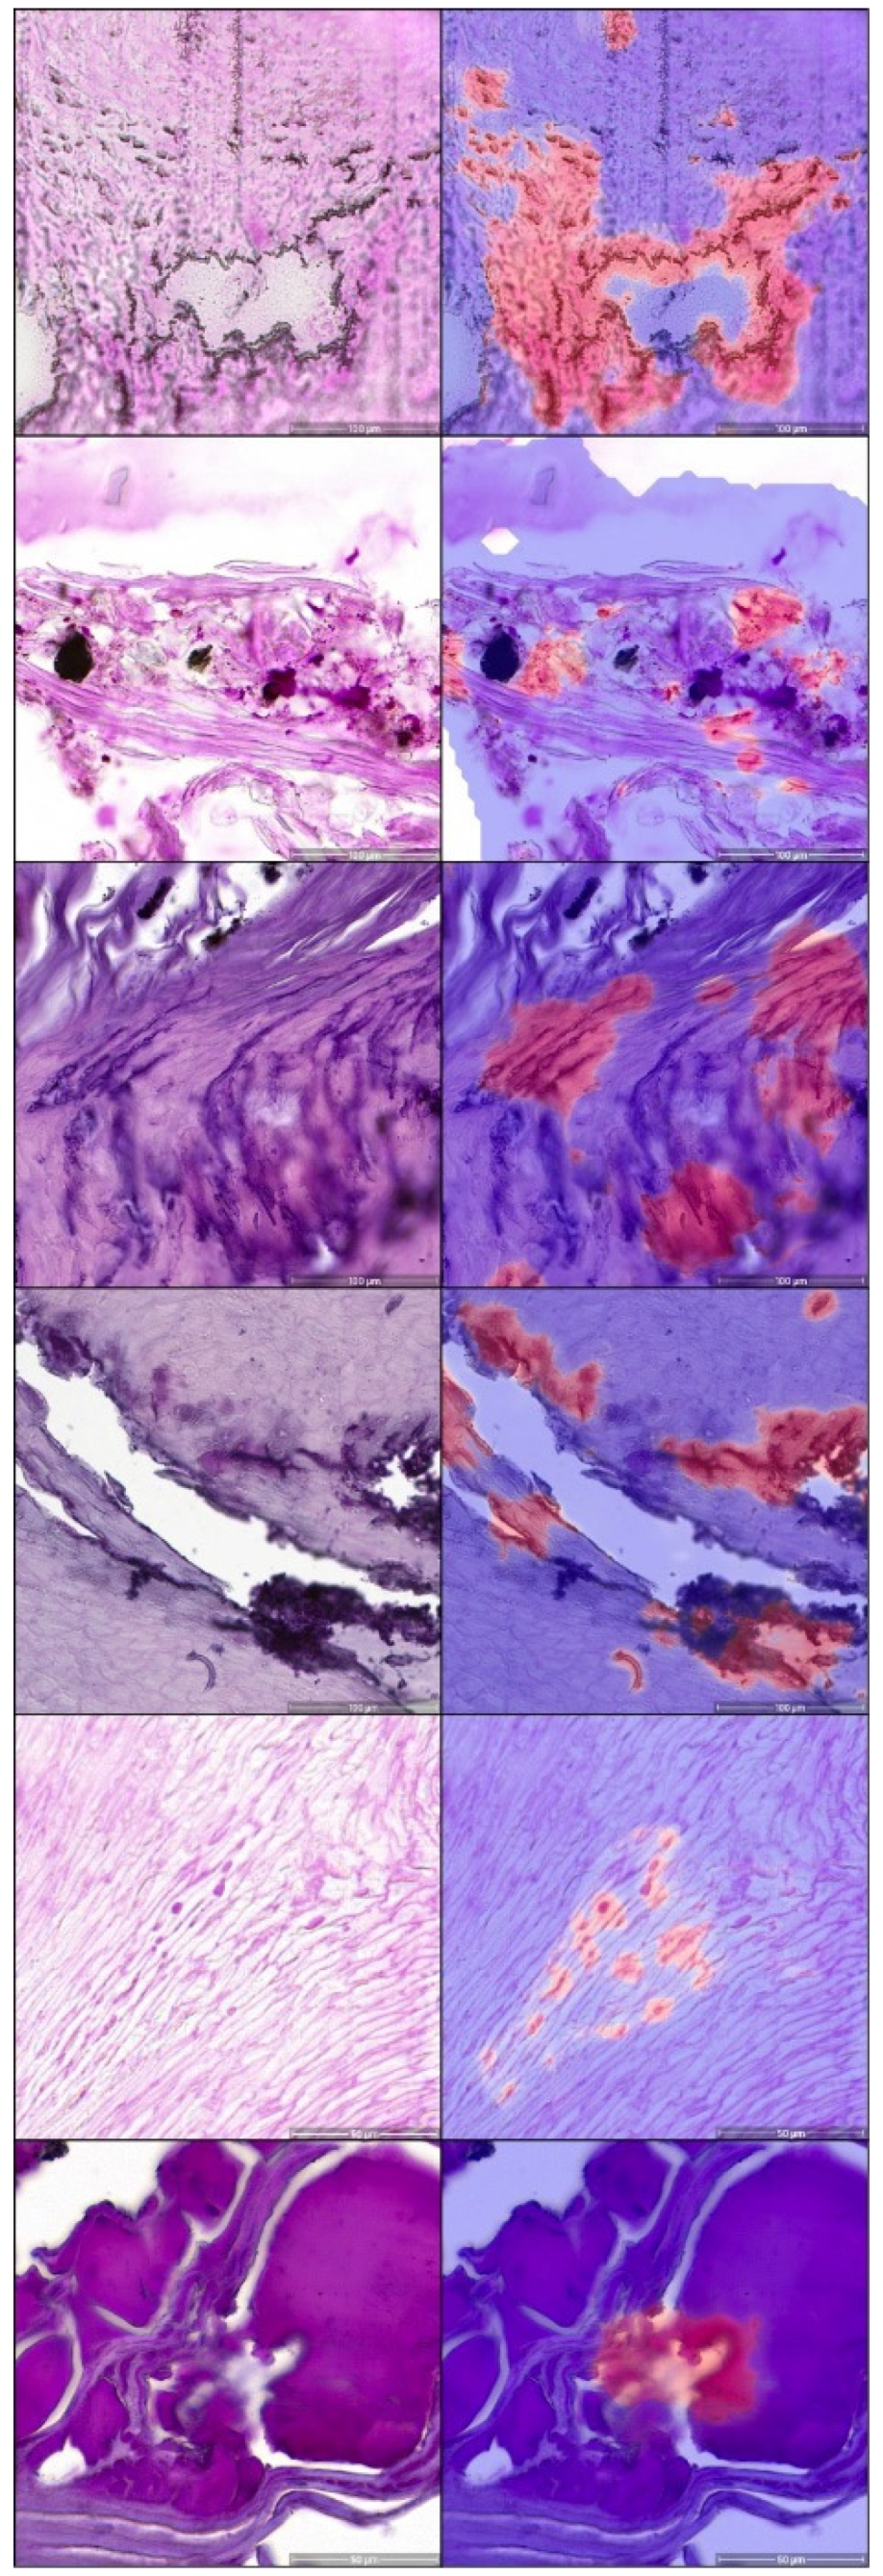

- Decroos, F.; Springenberg, S.; Lang, T.; Papper, M.; Zapf, A.; Metze, D.; Steinkraus, V.; Boer-Auer, A. A Deep Learning Approach for Histopathological Diagnosis of Onychomycosis: Not Inferior to Analogue Diagnosis by Histopathologists. Acta. Derm. Venereol. 2021, 101, adv00532. [Google Scholar] [CrossRef]